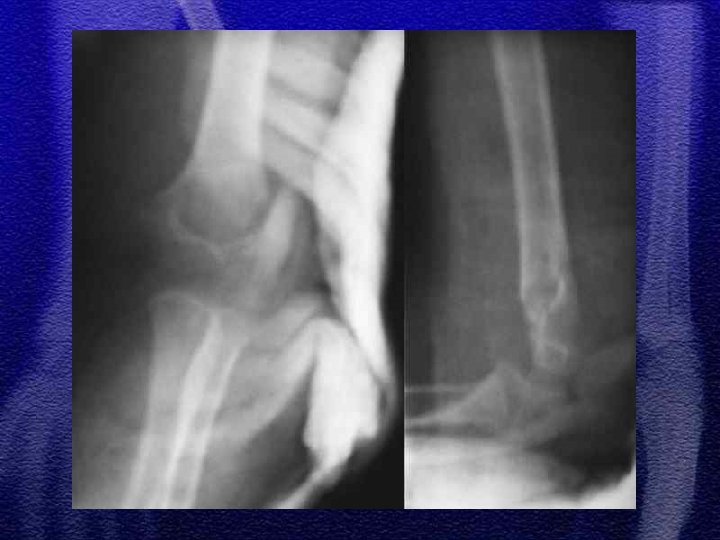

§ Zachowawcze - bez przemieszczenia oraz z przemieszczeniem kątowym do 20° § Repozycja zamknięta § Operacyjne - krwawe nastawienie i zespolenie śródszpikowe (drut Kirschnera) przeprowadzony przez dalszą nasadę kości ramiennej